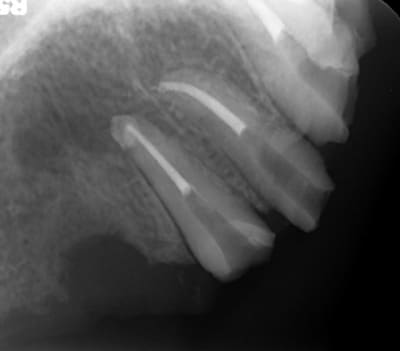

Mon petit cas galère du moment...

Péri-implantite 14 et 26.

25 explosée.

Infection apicale 13, 12, 33 (chaque 2 mois sous antibio depuis pas mal de temps...)

Et gros bouchon de fugy de 2 à 3 mm au fond du logement de l'inlay core, que j'ai dû traverser à la fraise diamantée pour pouvoir retraiter la 13 et la 12... :-)

Des pano comme ça, j'en vois tous les deux jours, avec des lésions apicales un peu partout.

Là, le dentiste (retraité depuis peu) a tout couronné, mis deux implants en plus pour rien, puis un stellite avec attachement (avec les implants en dessous qui ne servaient à rien...).

28/10/2014 à 23h43

jolies les endo! quel est le système que tu utilises ? gutta chaude ? système ??